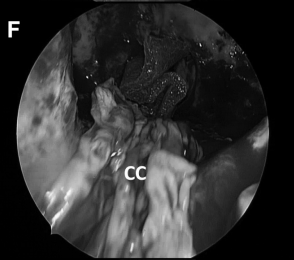

▼(F)可通过对侧入路通道、沿着肉芽肿病变长轴,利用吸引器和镊子,解剖分离病变包膜,达到次全切除病变的目的。

▼(L)使用鼻中隔瓣 (NSF)完成封闭。CC,囊包膜;PFD,后颅窝硬脑膜;S,蝶鞍;T,肿瘤。